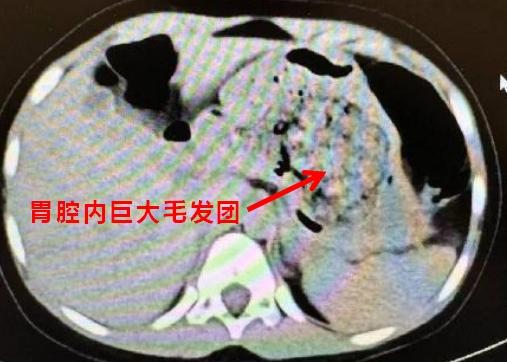

就医后医生发现孩子胃里面有一团密度较高的团块,结合母亲提供的病史,医生断定孩子长期吃头发导致了胃内毛发成团,这也是腹痛的原因。

可小朋友为啥会吃自己的头发?“这种长期喜欢吞食毛发的症状也被称为‘长发公主综合征’。”彭洪军告诉记者,“长发公主综合征”是一种罕见的疾病,被称为“拉庞泽尔综合征”,属于异食癖的一种。由于患者长期吞食毛发,导致毛发无法消化,并在胃肠道内大量聚集,形成坚固的异物团块,也是一种罕见的行为障碍,患者的自我控制能力较弱,会不自觉地咀嚼或吃掉自己的毛发,这些被摄入的毛发有时会在胃里滞留多年,最终形成毛石症。